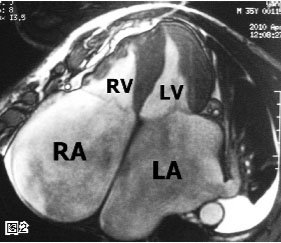

心肌淀粉样变一例

281x243 - 17KB - JPEG